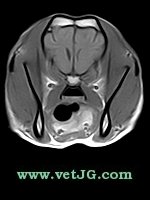

RESONANCIA MAGNÉTICA

TC

AXIAL